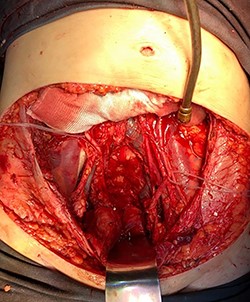

In April 2020, the surgery was performed, with pan-hysterectomy, excision of the AW and skin, pelvic peritonectomy, cecectomy (due to local involvement), partial cystectomy, Hartmann rectosigmoidectomy (Figs 4 and 5), followed by AW partial closure and an intraperitoneal onlay mesh (Open IPOM) in a bridged position with Bard Mesh/BD Sepramesh. Abdominoplasty was performed to allow skin coverage (Figs 6–10). The patient stayed in hospital for 18 days and presented urinary retention. Definitive anatomopathological was HGSC, infiltrating uterus, AW, cecum, rectosigmoid and obturator lymph node metastasis. After cytoreduction, she underwent chemotherapy (carboplatin plus docetaxel).

Surgical specimen of pan-hysterectomy with excision of the abdominal wall and cecectomy.

Pelvis after tumor excision, peritonectomy and lymphadenectomy.